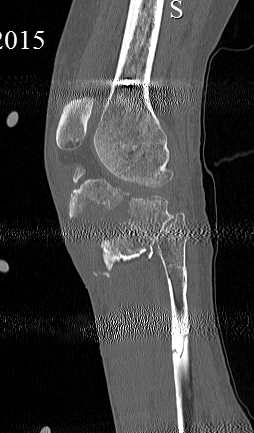

скан, который, на мой взгляд наиболее интересен

Серия КТ сканов в аппарате